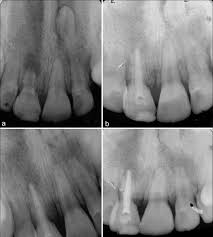

External root resorption treatment. If a dentist is able to spot the external symptoms and remove the cells causing damage in time you may not require any further dental care. Root resorption has been defined as the loss of dental hard tissue as a result of osteoclastic cell action 1 and can occur on both external and internal surfaces. If you can access then treatment with geristore or similar and possibly TCA for 1-4 minutes to remove tissue fragments.

The therapeutic measures which can regulate clastic activity include endodontic treatment the use of specific anticlastic agents such as Ledermix paste non-specific necrobiotic agents such as calcium hydroxide and trichloracetic acid surgery or root surface conditioners. External root resorptions are processes in which the loss of cementoblasts occurs causing the mineralized surfaces to be susceptible to the action of clastic cells. If you look at the tooth from the coronal view youll notice the location of the resorption is a little improved making it easy to understand why we call it external cervical resorption.

External resorption can be misdiagnosed.

However if more of the tooth structure has been affected a filling or root canal therapy might be the treatment of choice. Although it is predominantly detected by radiography in some cases root resorption may be identified by clinical symptoms such as pain swelling and mobility of the tooth. Patient was willing to try to save the tooth and took the second option. Sometimes it may be possible to repair the damage to the tooth but in some cases the only solution is to extract the. A second opinion may be necessary. In cases where the resorptive process is already established root canal treatment can arrest the resorption and encourage hard tissue repair. External root resorptions are processes in which the loss of cementoblasts occurs causing the mineralized surfaces to be susceptible to the action of clastic cells. External resorption can be misdiagnosed. External cervical resorption treatment options vary depending on the severity of the situation.

External Resorption Treatment ConsiderationsPrognosis Favorable Questionable Unfavorable External Resorption Minimal loss of tooth structure Located cervically but above the crestal bone The lesion is accessible for repair Apical root resorption associated with a tooth exhibiting pulp necrosis and apical pathosis Minimal impact on restorability of tooth. What is the treatment for dental resorption. The therapeutic measures which can regulate clastic activity include endodontic treatment the use of specific anticlastic agents such as Ledermix paste non-specific necrobiotic agents such as calcium hydroxide and trichloracetic acid surgery or root surface conditioners. If you look at the tooth from the coronal view youll notice the location of the resorption is a little improved making it easy to understand why we call it external cervical resorption. If a dentist is able to spot the external symptoms and remove the cells causing damage in time you may not require any further dental care. Root canal crown gum surgery tooth removal extraction. The treatment of root resorption is basically root and or periodontal endodontic treatment depending on the.